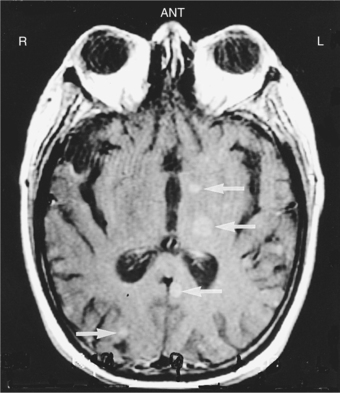

Overview and Incidence.: Primary CNS lymphoma (PCNSL) is a non-Hodgkin’s lymphoma and occurs in the absence of systemic lymphoma. It is also called an extranodal lymphoma. This tumor was formerly quite rare, but from 1973 to 1985 tripled in frequency in immunocompetent patients and also increased in the immunosuppressed population—that is, clients with acquired immunodeficiency syndrome (AIDS) and collagen vascular disorders, organ transplant recipients, and the congenitally immunodeficient.4,139 There was a decrease in incidence in young men and patients with AIDS from 1995 to 1998, explained by the introduction of highly active antiretroviral therapy for patients with human immunodeficiency virus (HIV) infection.142 It currently accounts for 4% to 7% of all primary brain tumors.1,26,28,58,91

Pathogenesis.: The pathophysiologic basis for development of these tumors is unclear, particularly in immunocompetent patients. PCNSL most commonly originates from B lymphocytes and is associated with cytokines. In immunosuppressed patients it is almost always associated with latent infection of neoplastic B cells by Epstein-Barr virus. B cells infected with Epstein-Barr virus are immortalized and able to replicate spontaneously.58 The lymphoma cells typically assume a periventricular pattern, involving the deep white matter, basal ganglia, corpus callosum, and thalamus. PCNSL may also involve the CSF, the eyes, or the spinal cord. A large percentage of PCNSLs begin as solitary cerebral lesions but eventually develop into multiple lesions. Lesions in immunocompetent patients more often may be a single brain lesion, in a supratentorial location, and with frontoparietal lobe involvement. The diagnostic procedure of choice is a stereotactic (x-ray guided) biopsy, because patients derive no clinical benefit from surgical resection.58

Clinical Manifestations.: Symptoms and signs generally evolve over several months, including personality and behavioral changes, confusion, generalized seizures, and symptoms associated with increased ICP (headaches, nausea and vomiting). The most frequent presenting symptom in 30% to 40% of patients is impaired cognition.32 Focal neurologic signs such as hemiparesis or blurred or double vision may occur. The appearance on MRI or CT of multiple deep cerebral and periventricular lesions, along with an immunodeficient state, contributes to the diagnosis.65 Differential diagnosis includes infections, other tumors, and inflammatory disorders.